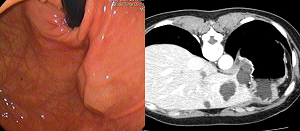

[Extrinsic compression due to liver cyst]